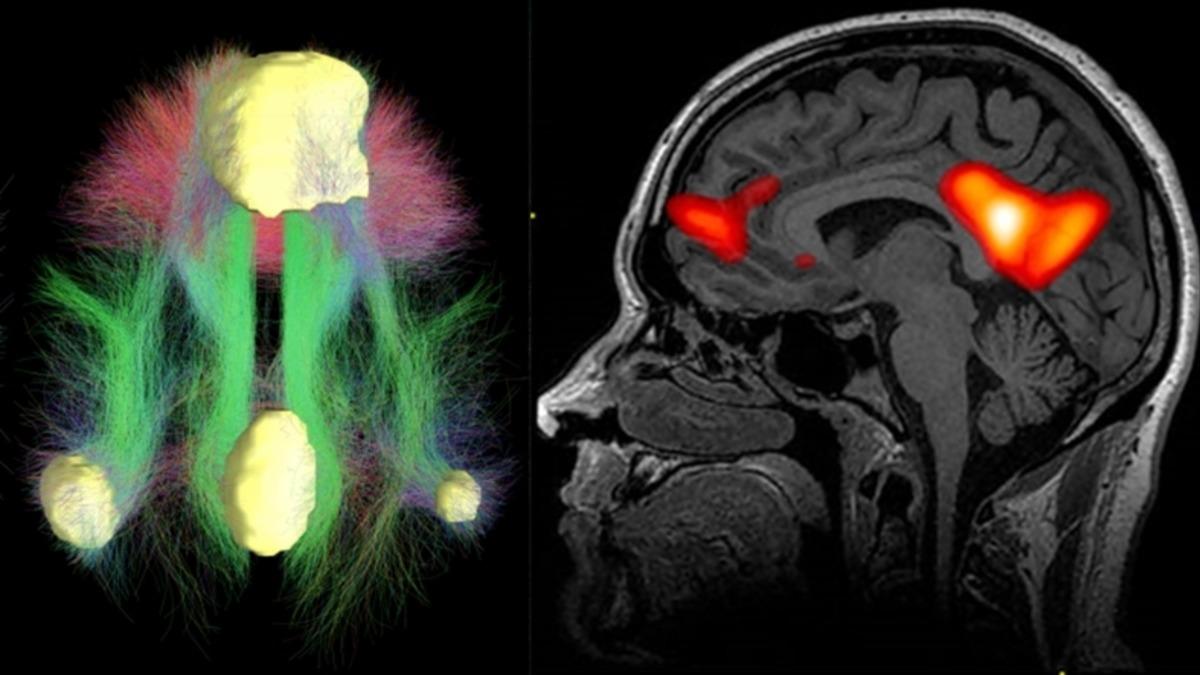

Bilim insanları, bu istemsiz dalıp gitmeyi bir hipotezle açıklıyor. Bu hipoteze göre, insan beyninde DMN (Default Mode Network) adı verilen bir ağ bulunuyor ve bu ağ, beynin diğer tüm bölgeleriyle etkileşime girdiğinde kişi, elinde olmadan uzaklara dalıp gitmelere başlıyor. Oldukça ilginç olan bu hipotezle ilgili detaylara ve daha fazlasına gelin, birlikte bakalım.

Bir kişi, çevresinde yaşanan şeylere karşı ilgisiz olduğunda veya tam odaklanmadığında, kişinin beyni uyanık bir dinlenme haline geçiyor. DMN denen bu ağ, insanlar geçmişlerini veya geleceklerini düşündüklerinde ve kendi içlerine kapanık bir hal aldıklarında da devreye girerek etkisini gösterebiliyor.

Yani bir nevi, yaptığınız işe tam olarak odaklanıp kendinizi vermediğinizde, beynin bu modu devreye girerek sizi bilinçsizce içinde bulunduğunuz durumdan uzaklaşmaya yönlendirir. Bu modun bir diğer adı da bilinçli bir seçim olmadan ortaya çıkan durum anlamına gelen ‘’Default Mode’’. Fakat şunu da söylemek gerekiyor ki DMN ile beynin dikkat ağları arasında pozitif bir korelasyon yok. Mesela bir kişi, yaptığı işe gerçekten özen gösterse bile bu, o işe ciddi anlamda dikkatini veriyor demek değildir. Yani sıkı ve dikkatli çalışan biri bile bazen dalıp dalıp gidebilir.